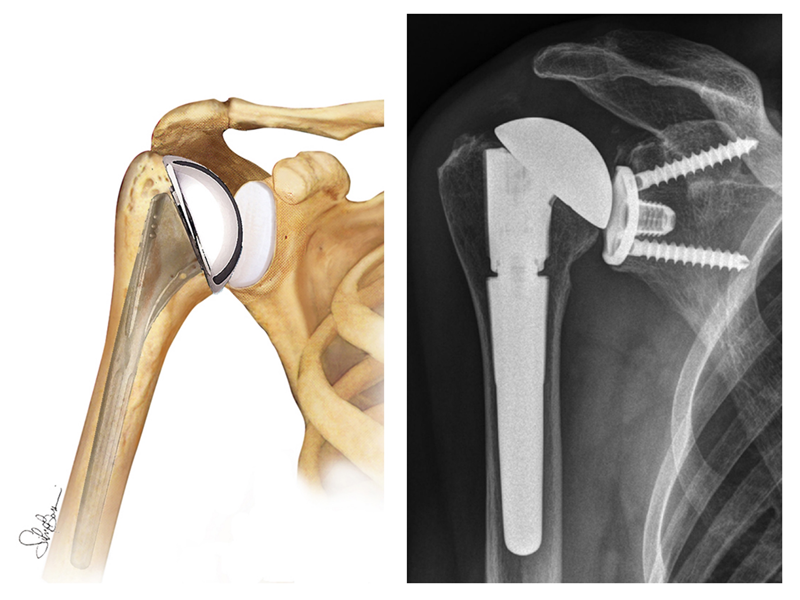

- Protesi totale di spalla (fig. 7): la tipica sostituzione totale della spalla comporta la sostituzione delle superfici articolari con elementi protesici in metallo e polietilene. I componenti sono disponibili in diverse dimensioni e possono essere cementati o non. Qualora l'osso fosse di buona qualità, il chirurgo può scegliere di utilizzare una componente omerale non cementata (press-fit); se invece l'osso si presentasse usurato, la componente omerale può essere impiantata con cemento. Nella maggior parte dei casi, viene impiantata anche una componente glenoidea in plastica.

- Endoprotesi di spalla: a seconda della condizione della spalla, il chirurgo potrebbe sostituire solo la testa omerale. Questa procedura è chiamata emiartroplastica. In una emiartroplastica tradizionale, la testa omerale viene sostituita da una componente protesica metallica costituita da uno stelo sul quale viene adagiata una sfera, riproducendo cosi le normali componenti anatomiche. L’emiartroplastica viene consigliata quando la testa omerale è gravemente degenerata ma le restanti componenti articolari sono normali.

- Protesi di spalla di rivestimento o “emicefalica” (fig. 8): comporta la sostituzione della superficie articolare della testa omerale con una protesi a cappuccio senza stelo. Può essere un'opzione valida se (a) la superficie articolare glenoidea è intatta; (b) il collo o la testa omerale non presentano fratture; (c) in pazienti giovani o molto attivi, evitando così i rischi di usura e allentamento delle componenti che potrebbero verificarsi con le sostituzioni convenzionali totali di spalla. Inoltre data la sua natura più conservativa, la protesi emicefalica può essere più facile da convertire in protesi totale di spalla quando necessario.

- Protesi inversa di spalla (fig. 9): un’altra opzione è rappresentata dalla protesi inversa di spalla, indicata per soggetti che presentano: (a) cuffia dei rotatori gravemente lesionata con perdita della forza e dell’arco di movimento; (b) articolazione gravemente artrosica; (c) fallimento di un precedente intervento di protesi totale di spalla. Importante chiarire che per questi soggetti all’intervento può seguire persistenza del dolore e una non totale riacquisizione dell’arco di movimento, soprattutto in abduzione. Nella protesi inversa di spalla, le convessità e le concavità articolari vengono invertite. Ciò significa che una sfera di metallo viene fissata alla glena e una superficie concava sostituisce la testa omerale.